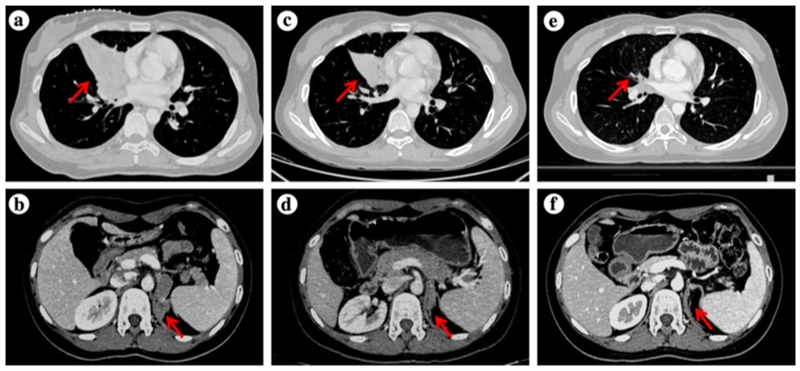

根据事先制定好的治疗方案,杨镇洲教授团队先后为患者进行化疗联合抗血管生成治疗、放疗、靶向治疗等,并定期做疗效评估以随时调整治疗方案。2020年5月第一次疗效评估:患者右肺中叶病灶较前缩小(由约54×42mm,缩小至约44×31mm),转移病灶均较前缩小,咳嗽显著缓解;2020年8月再次复查:右肺中叶病灶较前进一步缩小(大小约12×11mm),转移病灶也有不同程度缩减;胸部病灶放疗结束后,2020年10月复查提示原发灶及转移灶稳定,疗效评估为疾病稳定。

杨镇洲教授为患者王女士制定的精准化个体综合治疗使患者肿瘤病灶显著缩小(如下图),规律随访至今,疾病仍处于稳定状态。这充分说明基于分子诊断的个体化治疗及多学科讨论,可为有罕见基因突变分子事件的患者提供最佳诊疗方案。